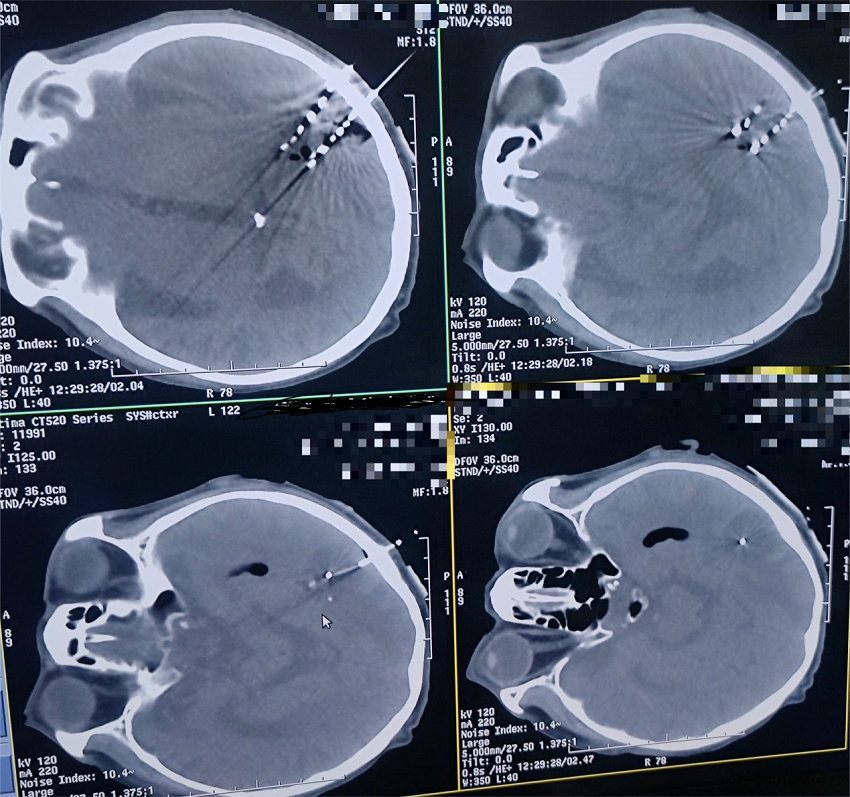

碘-125放射性粒子3D打印模版在颅脑肿瘤碘-125植入术

手术中